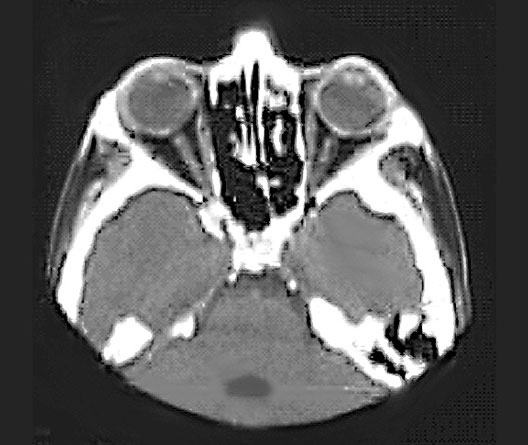

Head CT

1. Eyeball

2. Optic nerve

3. Nasal septum